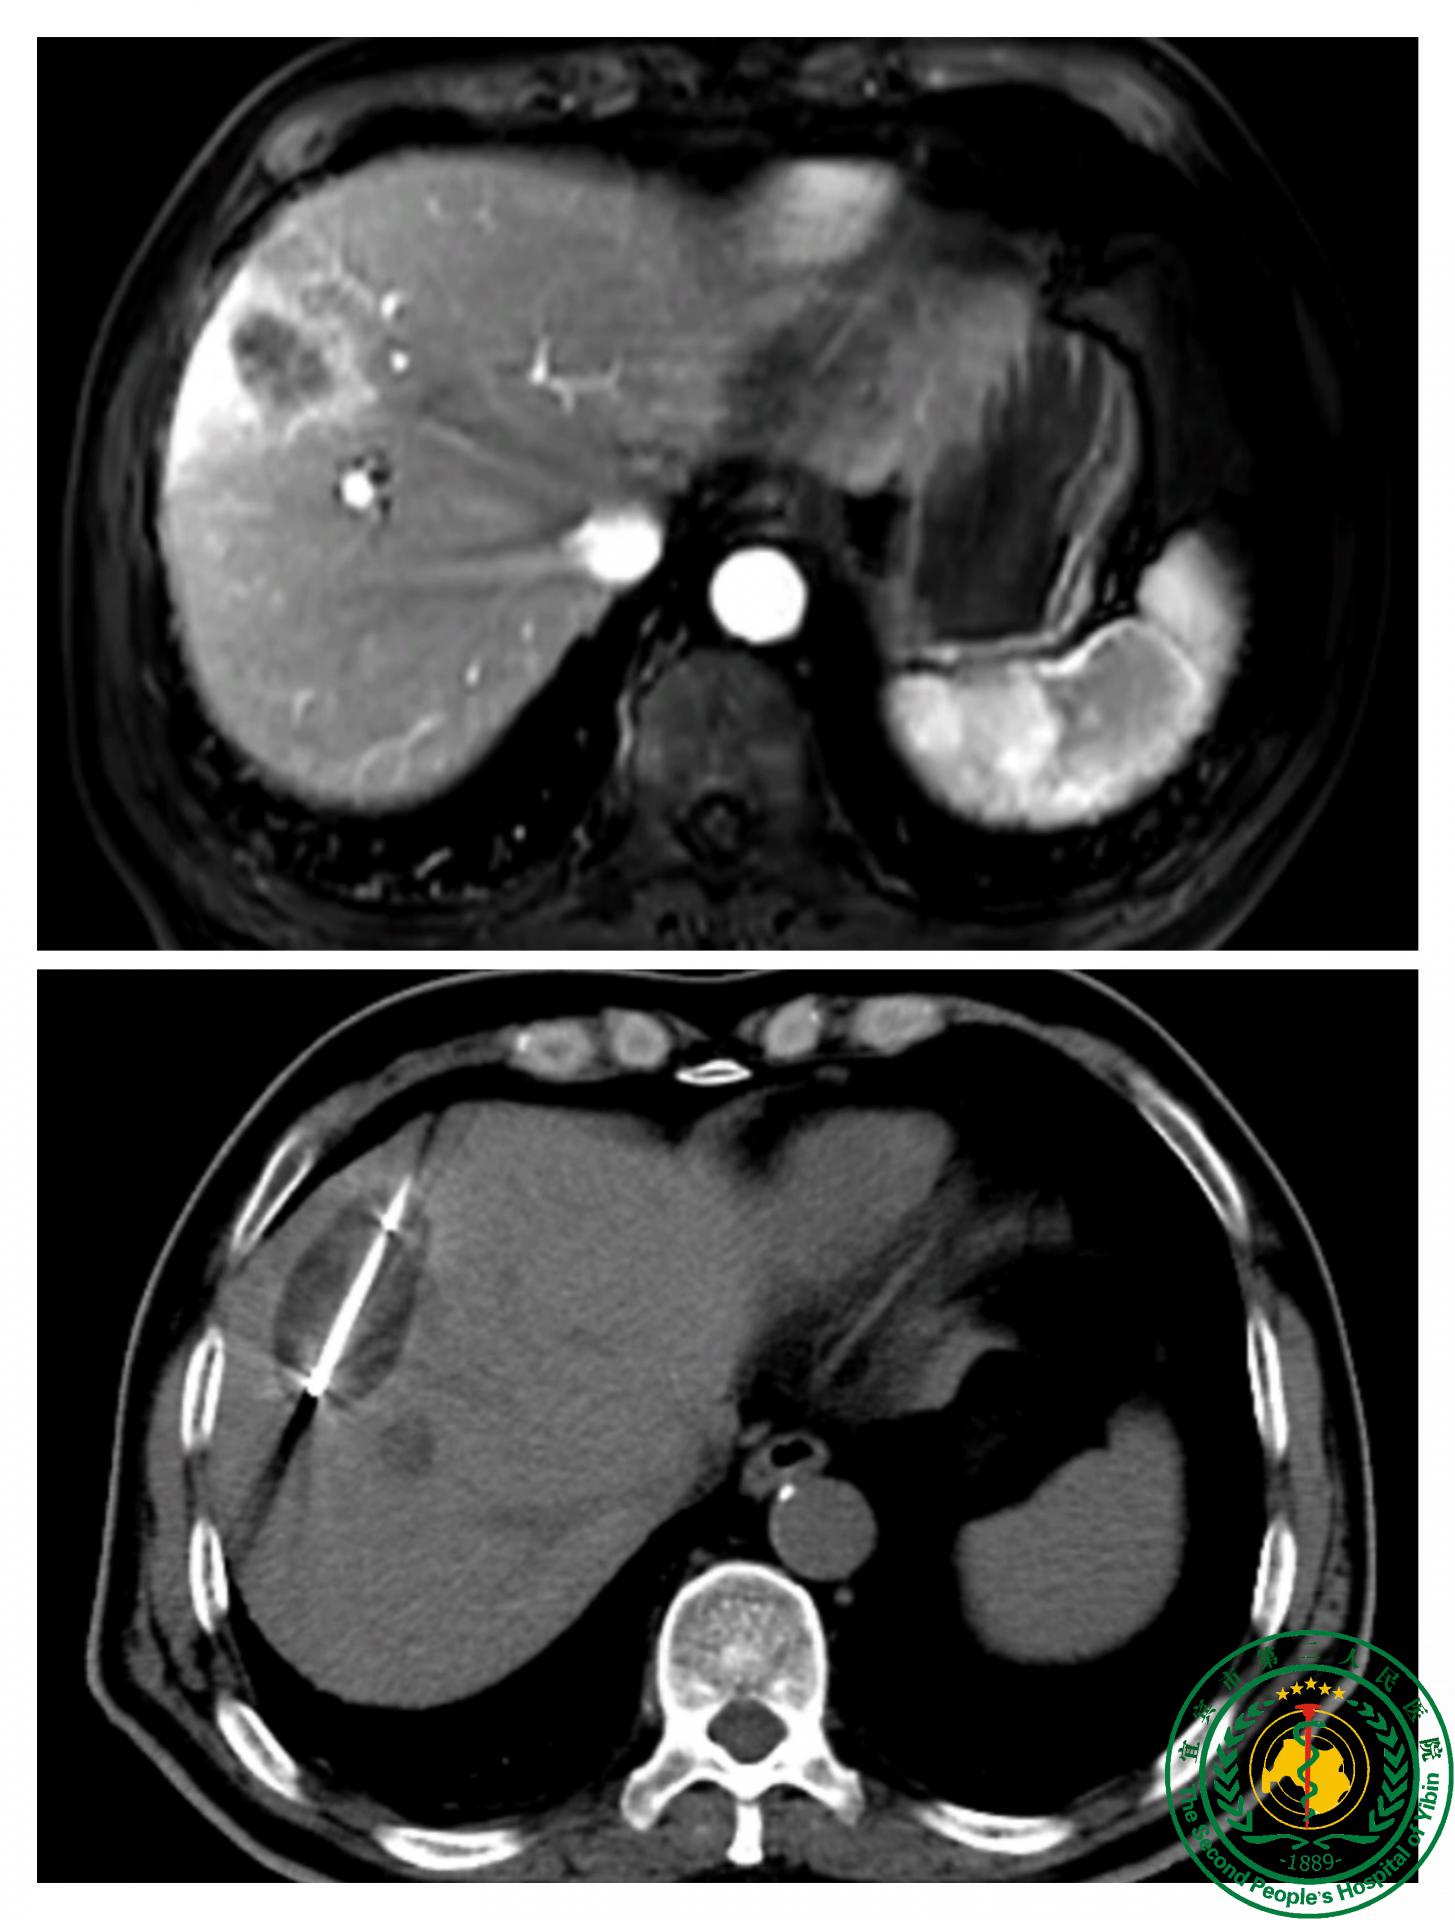

介入科顺利完成宜宾市首例经皮肝穿刺肿瘤冷冻消融治疗!

介入科顺利完成宜宾市首例经皮肝穿刺肿瘤冷冻消融治疗!51663